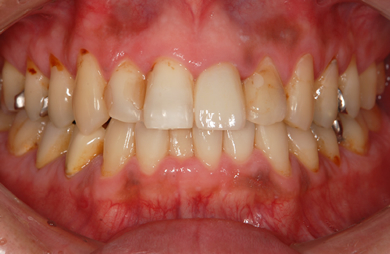

| 性別/年齢 | 男性 / 33歳 | ||||||||||||||||||||||||||||||||

| 主訴 | 痛みがある。 | ||||||||||||||||||||||||||||||||

| 治療方針 | 透明感のあるオールセラミックを使用して審美的・機能的回復を行う。 | ||||||||||||||||||||||||||||||||

| 治療内容 | オールセラミック6本(オールセラミック用の土台2本) | ||||||||||||||||||||||||||||||||